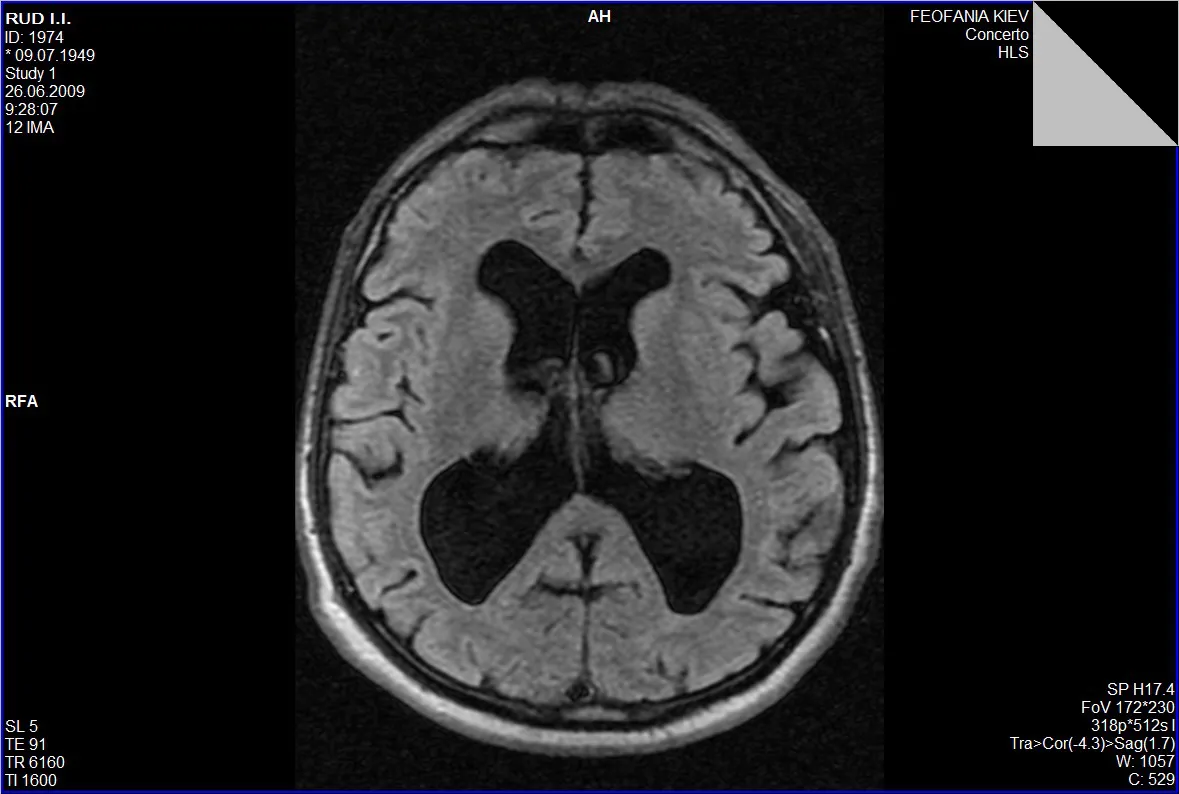

Гідроцефалія, або водянка головного мозку, — це патологічний стан, який характеризується накопиченням цереброспінальної рідини (ліквору) у шлуночках мозку та міжоболонкових просторах.

Запідозрити гідроцефалію можна на підставі виявлення скарг на головний біль, запаморочення, нудоту, порушення зору, порушення координації руху кінцівок, зниження пам’яті, уваги та інших когнітивних здатностей, порушення функції тазових органів (нетримання сечі).

Звернутися з метою обстеження та верифікації діагнозу гідроцефалії із наступним нейрохірургічним втручанням ви можете Центрі Нейрохірургії «Оберіг». До переліку обстежень входить стандартний лабораторний пакет загальноклінічних аналізів та МРТ головного мозку.